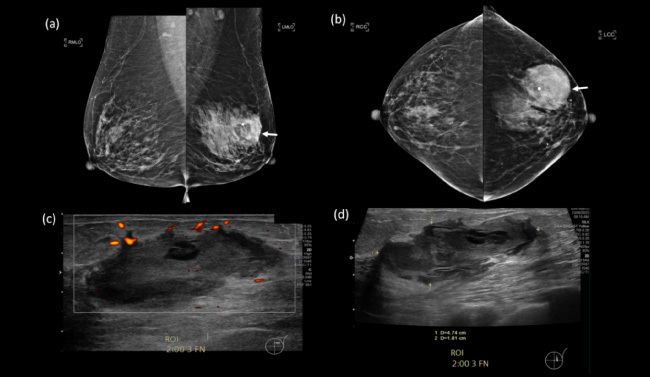

An 85-year-old Chinese lady presented with a 5-day history of a painless left breast lump. There was no fever, nipple discharge, or history of trauma. She had a past medical history of atrial fibrillation that was managed with an oral anticoagulant. Mammography demonstrated a dense mass in the upper outer quadrant of the left breast. Ultrasound showed an irregular, heterogeneous 4.7 cm lesion containing debris and cystic spaces with raised peripheral vascularity at the 2 o'clock position, 3 cm from nipple. No internal vascularity was detected. This was managed as a haematoma and rivaroxaban was withheld. Follow-up imaging 3-weeks later showed persistence of the lesion. Bedside needle aspiration yielded haemoserous fluid with immediate reduction in size of the lesion. However, 2 weeks after aspiration, there was recurrence of the 'haematoma'. Multidisciplinary review of the clinical history, examination and imaging was sought, and biopsy of the irregularly thickened areas with vascularity along the periphery of the lesion was recommended. Vacuum-assisted biopsy was performed, and histology returned as metaplastic carcinoma. A recurring 'haematoma' should always prompt a search for a secondary cause, with features such as irregular thickened walls and papillary/nodular components requiring further evaluation with biopsy for histopathological correlation.